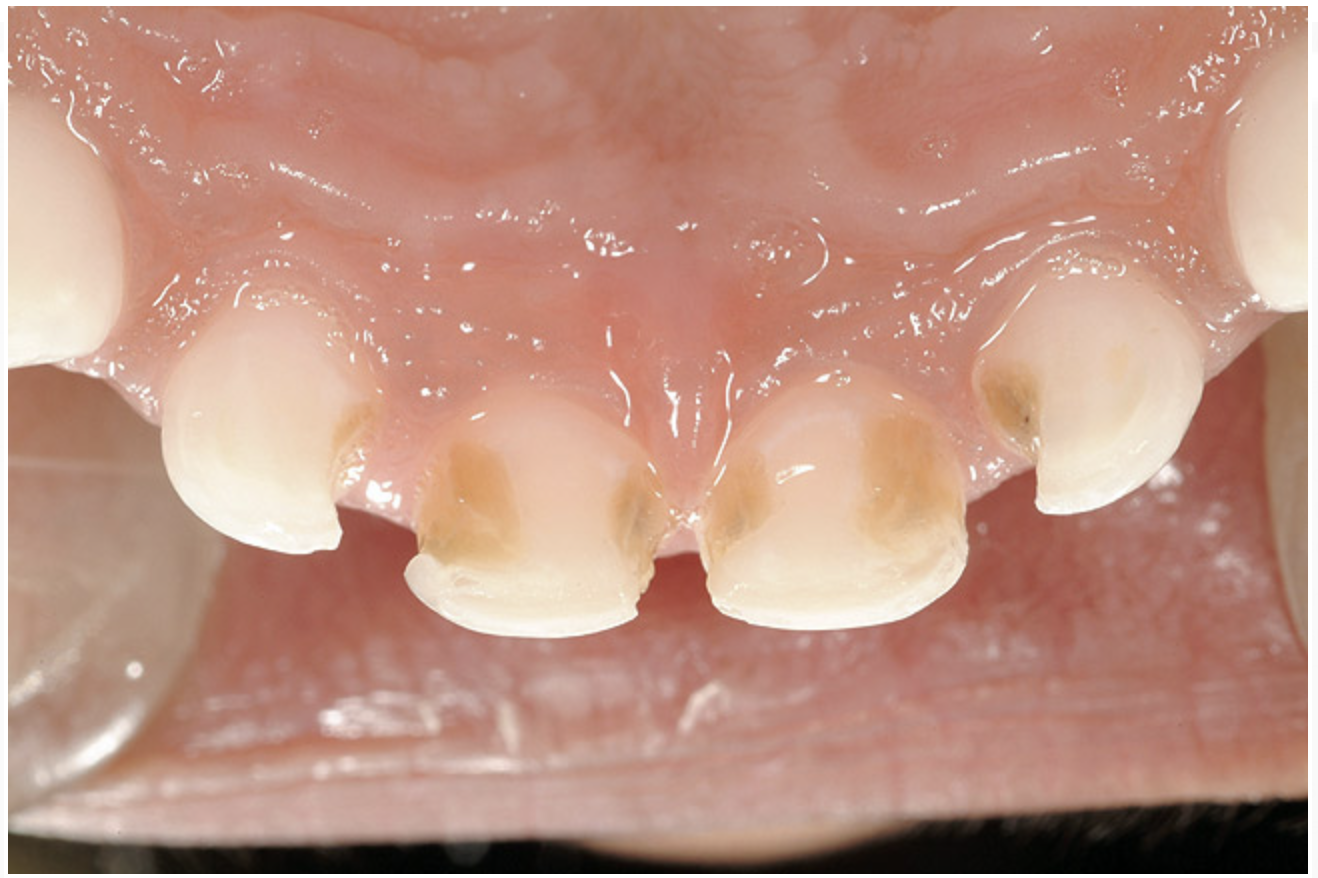

The characteristics of ECC (Figure 2) are:

1. It develops rapidly. Progression from the enamel into the dentin occurs in 6 months or less.

2. It affects the upper front teeth first. These teeth usually erupt at around 8 months of age.

3. Primary molars, which begin to erupt at about 12 months of age, are the next teeth to be affected.

4. Finally, the lower front teeth are affected when the disease becomes very severe.

As the condition worsens, white-spot lesions develop into larger caries lesions. The time frame from early decay to later decay can be as short as 6 to 12 months. At this point, the child may complain about toothache when extremely cold foods are eaten. As the caries process continues, the lesions will appear as brown/black collars around the gingival margin. The child will often begin to indicate the presence of pain.

The time frame from later to severe decay can be as little as 6 weeks. This is because once the decay penetrates through the hard outer enamel layer of the tooth and enters the dentin, it progresses very quickly.